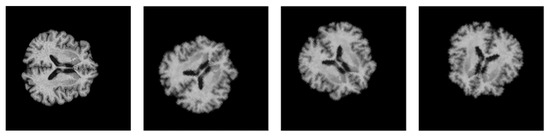

4.3. Data Augmentation

To improve the generalizability of the proposed model and expose new variations during training, online augmentation was performed on the 2D samples. The dataset was augmented by applying random geometric transformations such as flipping and rotation. The parameter range for the random rotation function is in the range of 0° to 90°, and the probability of random horizontal and vertical flips is set to 50% each. Figure 7 depicts the augmented brain MRI images. Furthermore, class imbalance was also solved using data augmentation. All the transformations were carried out using the Torchvision library.

Figure 7. Visualization of the augmented brain MRI images.